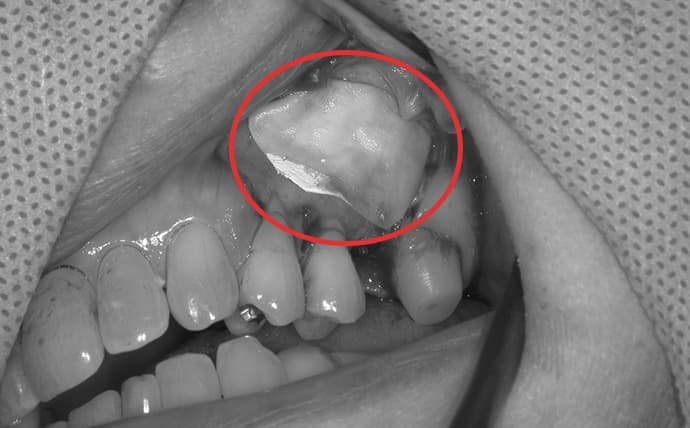

抜歯即時埋入

抜歯が必要な歯に対し、抜歯と同時にインプラントを埋入する治療法です。通常必要となる治癒期間を待つことなく治療を進められるため、治療期間の短縮が期待できます。